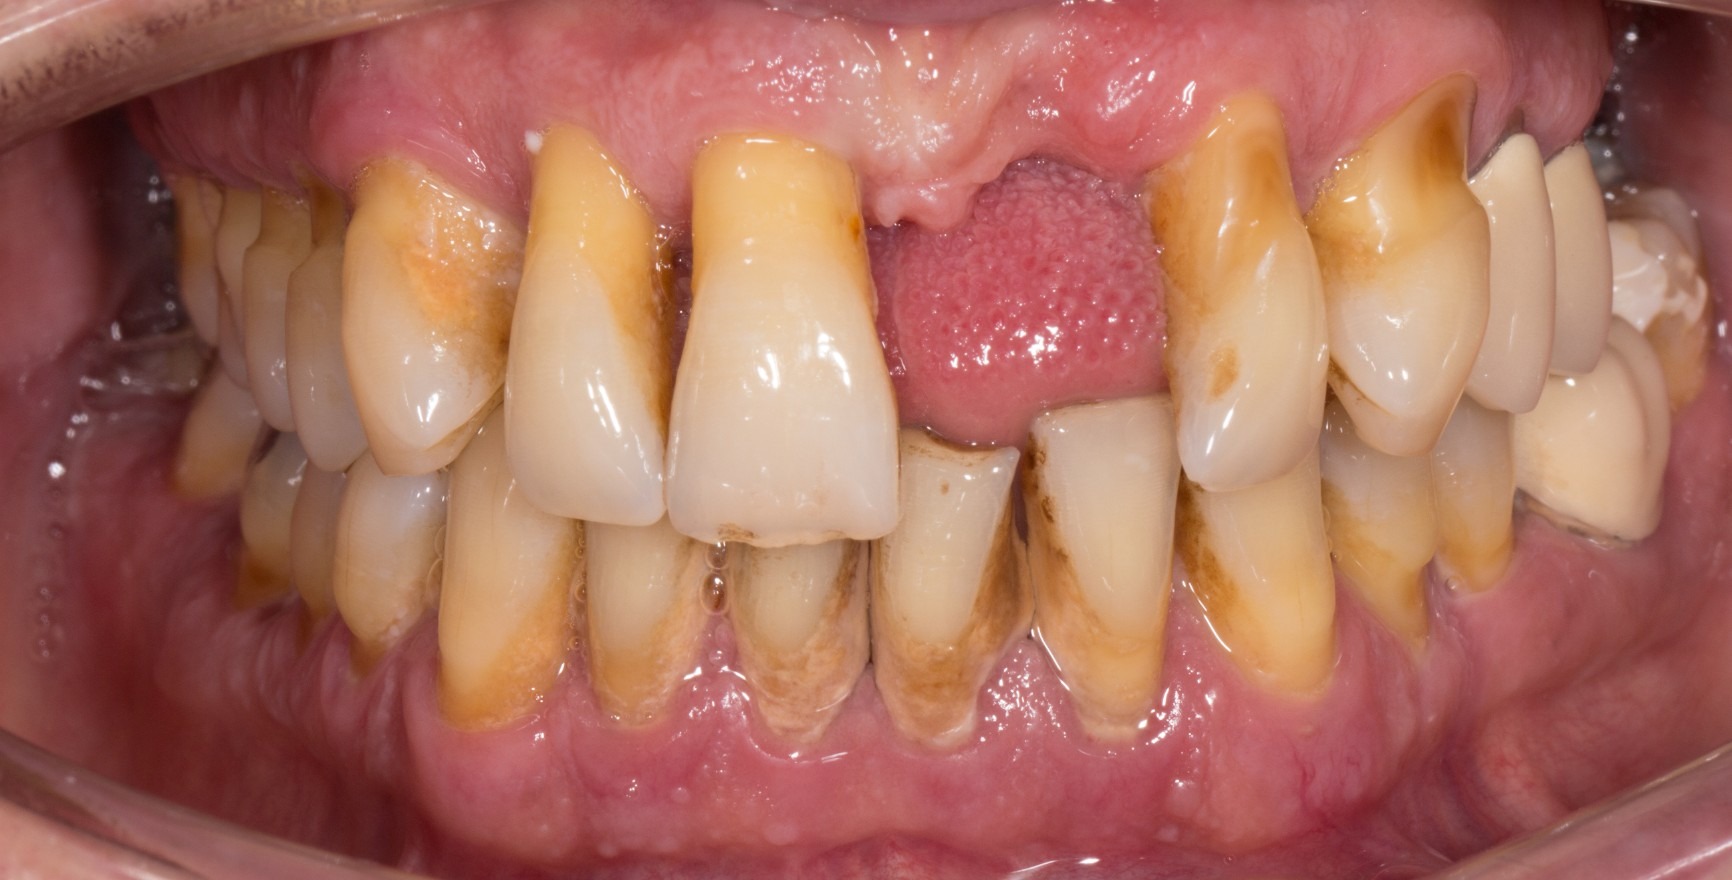

For the first time, the new classification scheme for periodontal diseases, which was presented in June 2018, contains a definition of the concept of clinical periodontal health (Lang & Bartold, 2018). Even under optimum hygiene conditions, a small quantity of bacterial biofilm is present in the gingival sulcus. A complete absence of bacteria is not possible under clinical conditions. The histological response to this is a limited subepithelial infiltrate of neutrophilic granulocytes (PMN). However, providing homeostasis is maintained between the biofilm and a small quantity of PMN infiltrate, this state is seen as an expression of immunological control and thus as a physiological process, not a pathological (inflammatory) one (Brecx et al., 1987a+b). The microbiological load and host factors determine whether the state of clinical periodontal health continues. Locally, these can lead to an increased accumulation of biofilm (e.g. inadequate dental restorations or unfavourable tooth positions) or they can affect the immune response (e.g. systemic diseases).

A state of clinical periodontal health in the intact periodontium is distinguished from that in a reduced periodontium already affected by clinical loss of attachment. This loss of attachment can occur:

as result of inflammation during the course of periodontitis. Clinical periodontal health then describes a stable condition after successful completion of periodontal treatment.

The clinical criterion is always the absence of bleeding on careful probing (bleeding on probing = BoP). A distinction is made between a site/tooth-specific diagnosis with a negative BoP finding at the corresponding measurement site, and diagnosis on the level of the tooth or patient, for which a threshold value of a BoP ≤ 10% still meets the criteria of clinical periodontal health. Pocket probing depths must be no more than 3 mm. In a reduced periodontium after periodontal treatment, a threshold value of 4 mm is still regarded as a stable status (Matuliene et al., 2008).

If a diagnosis of ‘clinical periodontal health’ is made, the patient’s history must be taken into account to ensure their correct future care: periodontitis is a chronic disease that can be successfully controlled by means of treatment. Unlike for fully reversible gingivitis, however, even if the patient has a stable condition after periodontitis treatment, they are nonetheless at an increased risk of further loss of attachment. The periodontitis patient will remain a periodontitis patient for the rest of their life and will therefore need long-term periodontal maintenance therapy (PMT).